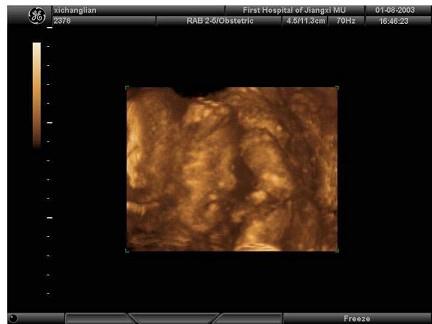

女性,25岁,停经35周。产前超声检查,图像显示的是胎儿的?(?)A.脊柱B.四肢C.颜面部D.胸腔E.腹腔

问题 女性,25岁,停经35周。产前超声检查,图像显示的是胎儿的?(?)

选项 A.脊柱 B.四肢 C.颜面部 D.胸腔 E.腹腔

答案 C